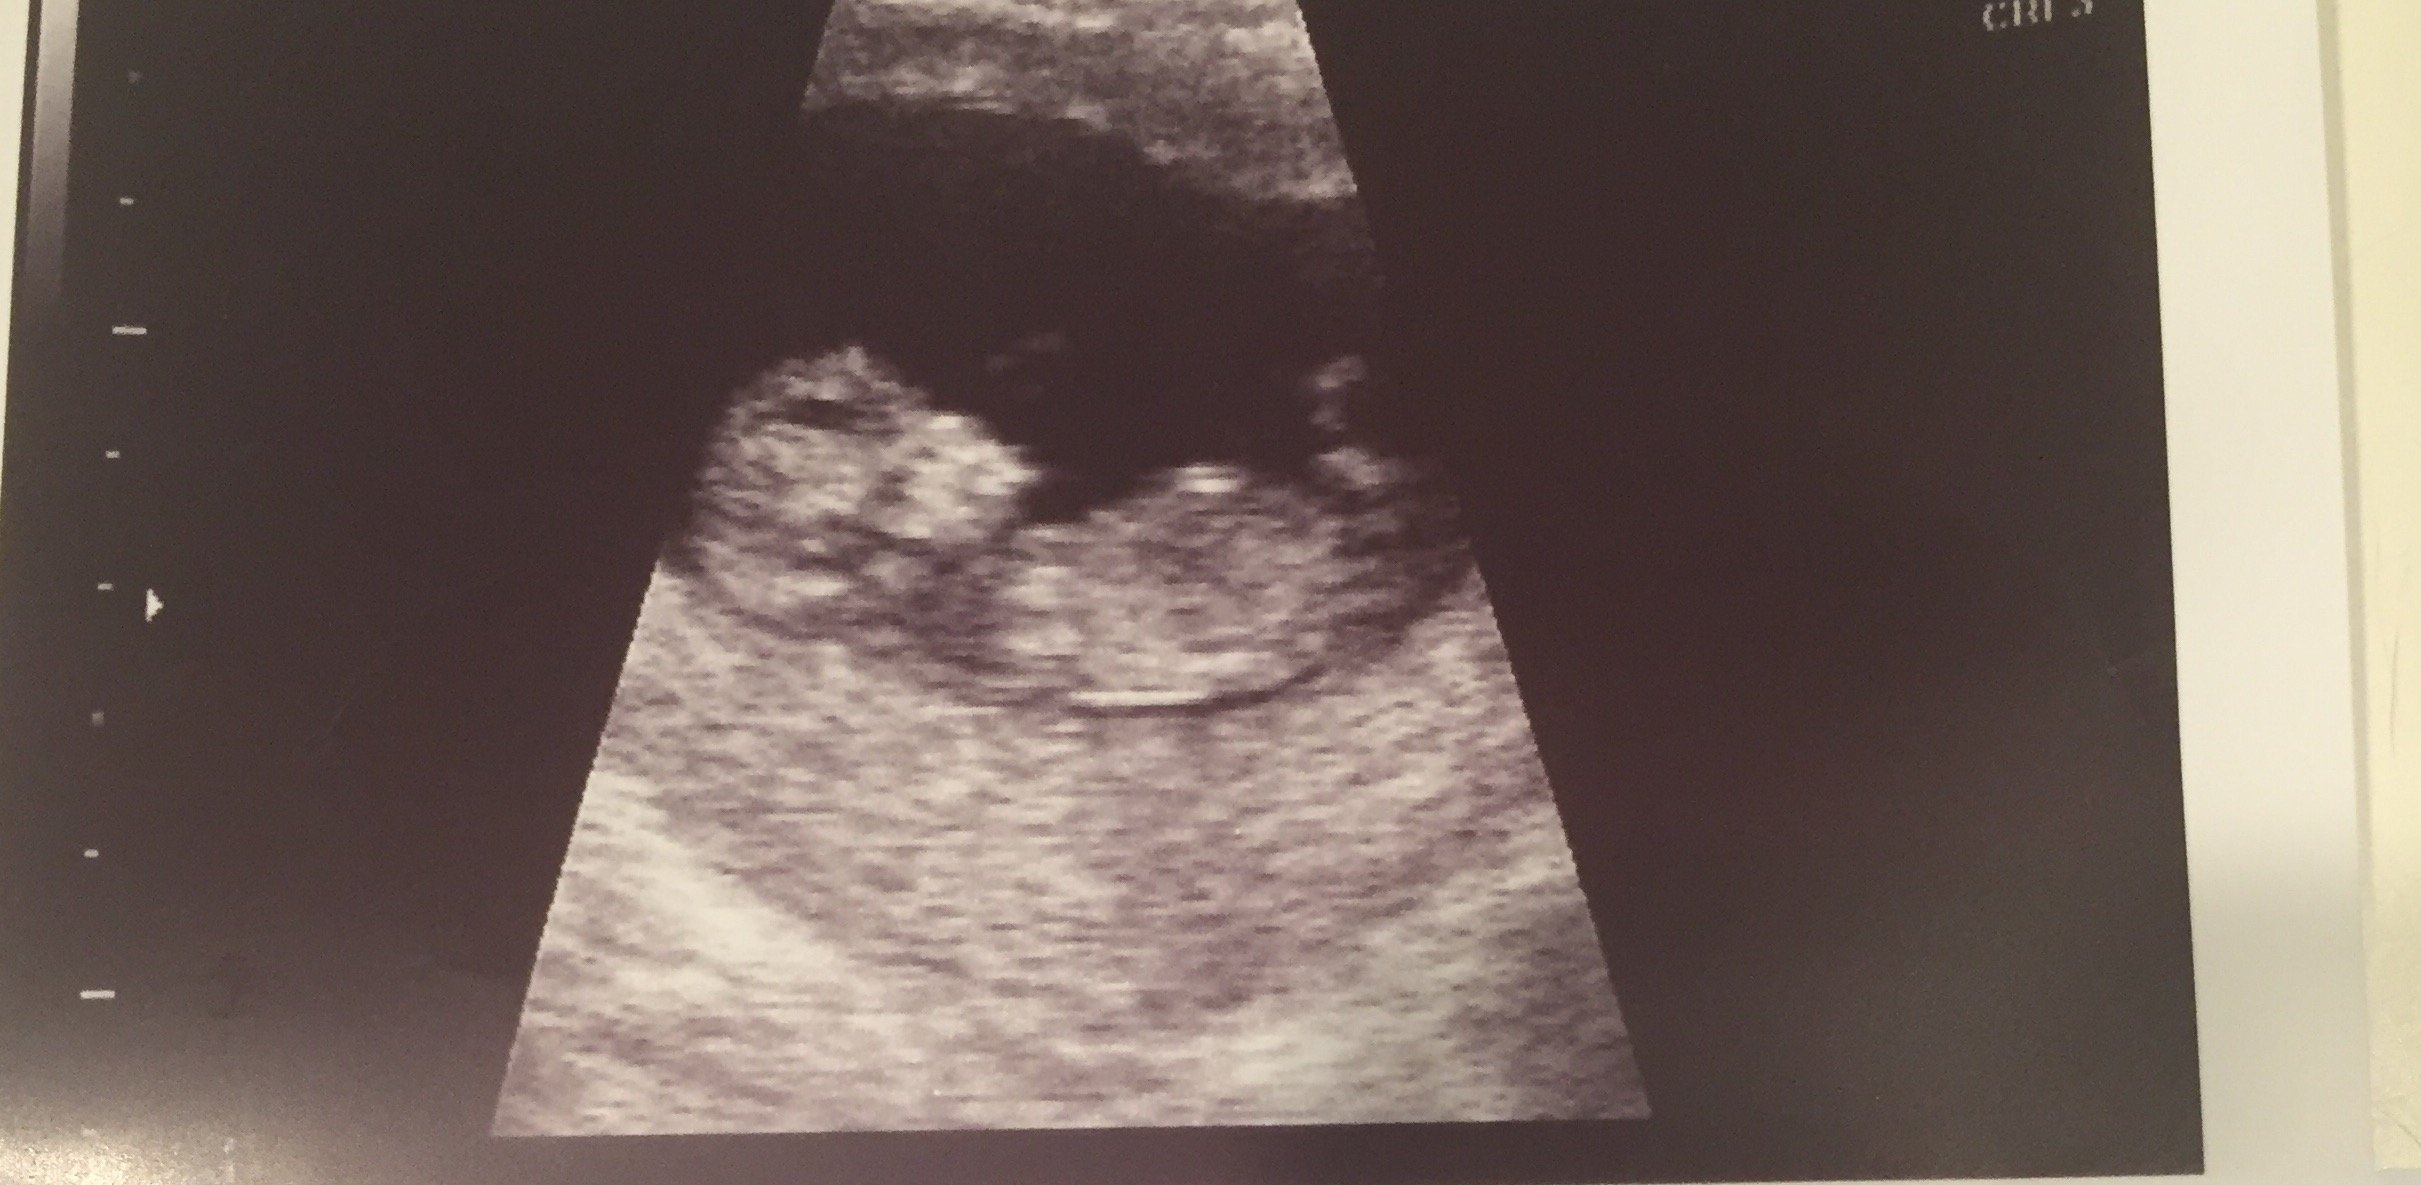

Had my first obgyn today at 11 weeks, 2 days. Pap smear and they told me

I wasn't scheduled for an US today so I begged the midwife if we can at

least hear the heart beat. Well she couldn't find it but said that's

not unusual. So she said in these cases we will do an US. I got to see

baby and he/she was so active and jumping around everywhere. His

heartbeat is good. I also asked if she did the Neck test which I thought

was for downs syndrome but the US person said it was for heart

defects. huh? what? Now I'm confused if they ever tested for downs

today. Anyway, then they took 7 vials of blood and waiting on those

blood results now. Once we get those back I think we will start telling

our friends. It was literally a 3 hour appt for me. Now I don't go back

for a month. US pic coming soon!